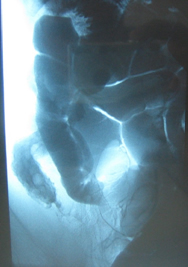

Στους ίδιους ασθενείς η εντερόκλυση μπορεί να αναδείξει ανάλογα ευρήματα με την ενδοσκοπική κάψουλα (εικόνες 36-43) ή να είναι φυσιολογική (εικόνες 44-48).

38  39

Εικόνα 38. Ο ίδιος ασθενής με τις εικόνες 10,13.          Εικόνα 39. Ο ίδιος ασθενής με τις εικόνες 33,34.

Στένωση τελικού ειλεού                                                  Εξελκώσεις τελικού ειλεού